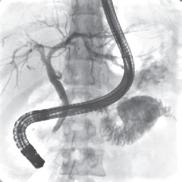

“This is a good example of a problem I’m having clinically that’s being solved by our research group,” says radiologist and scientist, Shane Wells, MD, Associate Professor of Radiology and Urology whose research focuses on improving diagnostic information to help urologists make more informed decisions. “I currently use ultrasound or CT to put needles into the liver to treat tumors. The needles get hot at the end and burn the tumor. It’s a minimally invasive procedure that can actually cure liver cancer and patients can go home the same day. However, one of the shortcomings of the current technology is that we can’t target tumors very well, which negatively affects patient outcomes. Now, the platform that we’ve developed at MIITT combines ultrasound and MRI to improve that tumor targeting.”